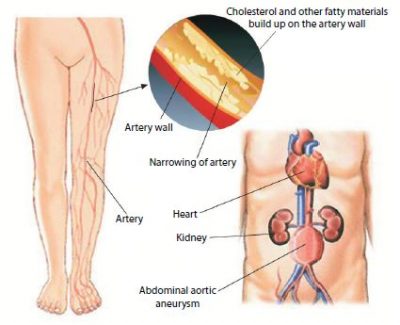

【公式】フジのお歳暮・冬ギフト - WEBカタログ掲載中 515op2i0+AL._AC_UF1000, 健康・医学

515op2i0+AL._AC_UF1000,,

515op2i0+AL._AC_UF1000,, Vascular and Endovascular Surgery - Surgery | UCLA Health,

Vascular and Endovascular Surgery - Surgery | UCLA Health, Comprehensive Vascular and Endovascular Surgery | ScienceDirect,

Comprehensive Vascular and Endovascular Surgery | ScienceDirect, Vascular Surgery and Endovascular Therapy - FV Hospital,

Vascular Surgery and Endovascular Therapy - FV Hospital, Vascular Surgery Books, eBooks & Journals | US Elsevier Health